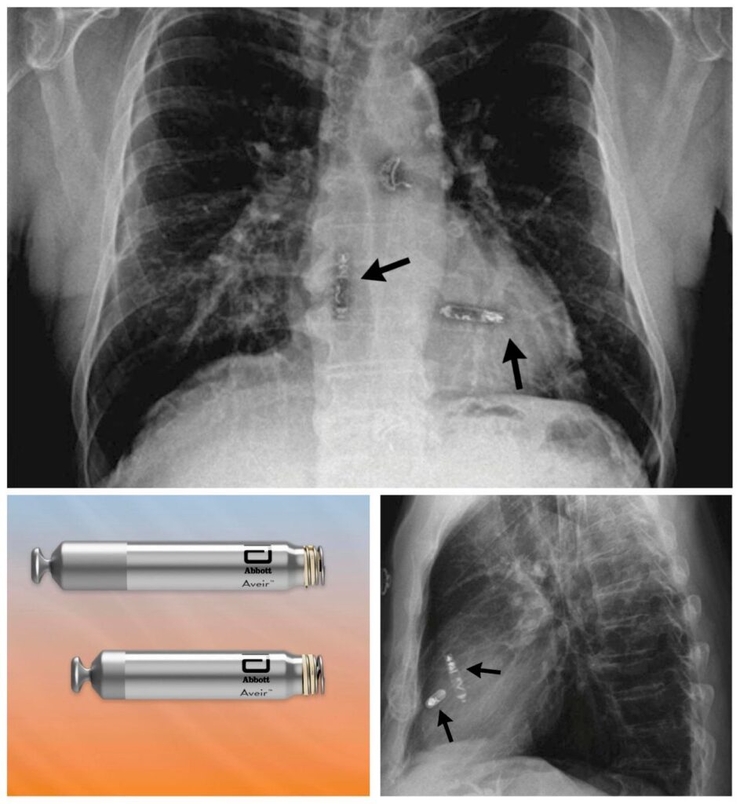

The leadless pacemaker is inserted through a catheter, with no wires or visible scarring, from the top of the leg in the groin region through the skin.

Two small 'bullet-sized' devices are placed in each chamber, syncing together wirelessly using electrical impulses.

"The technology is especially useful for patients with limited vascular access or at high risk of infection in cases where traditional pacemaker systems cannot be used," A/Prof Wong said.